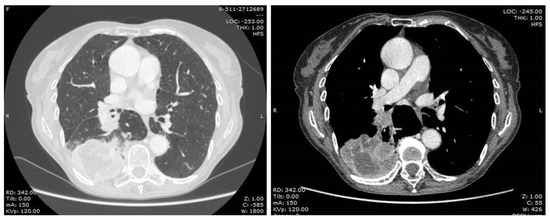

A 76-year-old female patient was admitted to our surgical department in January 2021. She was a current smoker (45 pack-year), affected by an atrial septal aneurysm (ASA), obstructive pulmonary disease (COPD), mixed anxiety-depressive disorder (MADD), gastroesophageal reflux disease (GERD), osteoporosis. Furthermore, she had a history of cerebral vascular disease with a previous transient ischemic attack in 2010. Her previous surgeries were a cholecystectomy, a hernioplasty, and a benign breast nodule excision. Her home therapy included escitalopram, lysine acetylsalicylate, esomeprazole, and cholecalciferol. She was referred to our unit for the management of a large lung mass, revealed by a routine chest X-ray. The preoperative computed tomography (CT) scan (Figure 1) showed a lesion in the right lower lobe (69 × 54 × 76 cm) with suspected infiltration of costal pleura and distal occlusion of the bronchus intermedius associated with hilar lymphadenopathy. Therefore, positron emission tomography (PET) CT scan detected increased glucose metabolism exclusively in the lung mass (SUV max 24.08) and in the right hilar lymphadenopathy (SUV max 22.48). The bronchoscopy image showed endobronchial vegetation occluding the apical segment of the right lower lobar bronchus. Histological examination of bronchial biopsy revealed a lung adenocarcinoma wild-type with a PD-L1 expression of 30%. Last, a cranial CT scan was performed and it was negative for brain metastasis. The clinical staging of the tumor resulted in cT4N1M0. The patient performed global spirometry, which revealed a mild obstructive ventilation defect, with a forced expiratory volume in one second (FEV1) of 1.70 L (105%) and a Tiffeneau index of 0.64. The cardiological evaluation did not detect pathological conditions, and the electrocardiogram showed sinus rhythm and regular QT interval. The invasive mediastinal staging was performed through EBUS-TBNA, which did not reveal any mediastinal positive lymphadenopathy.

Figure 1.

Pre-operative chest CT-scan.